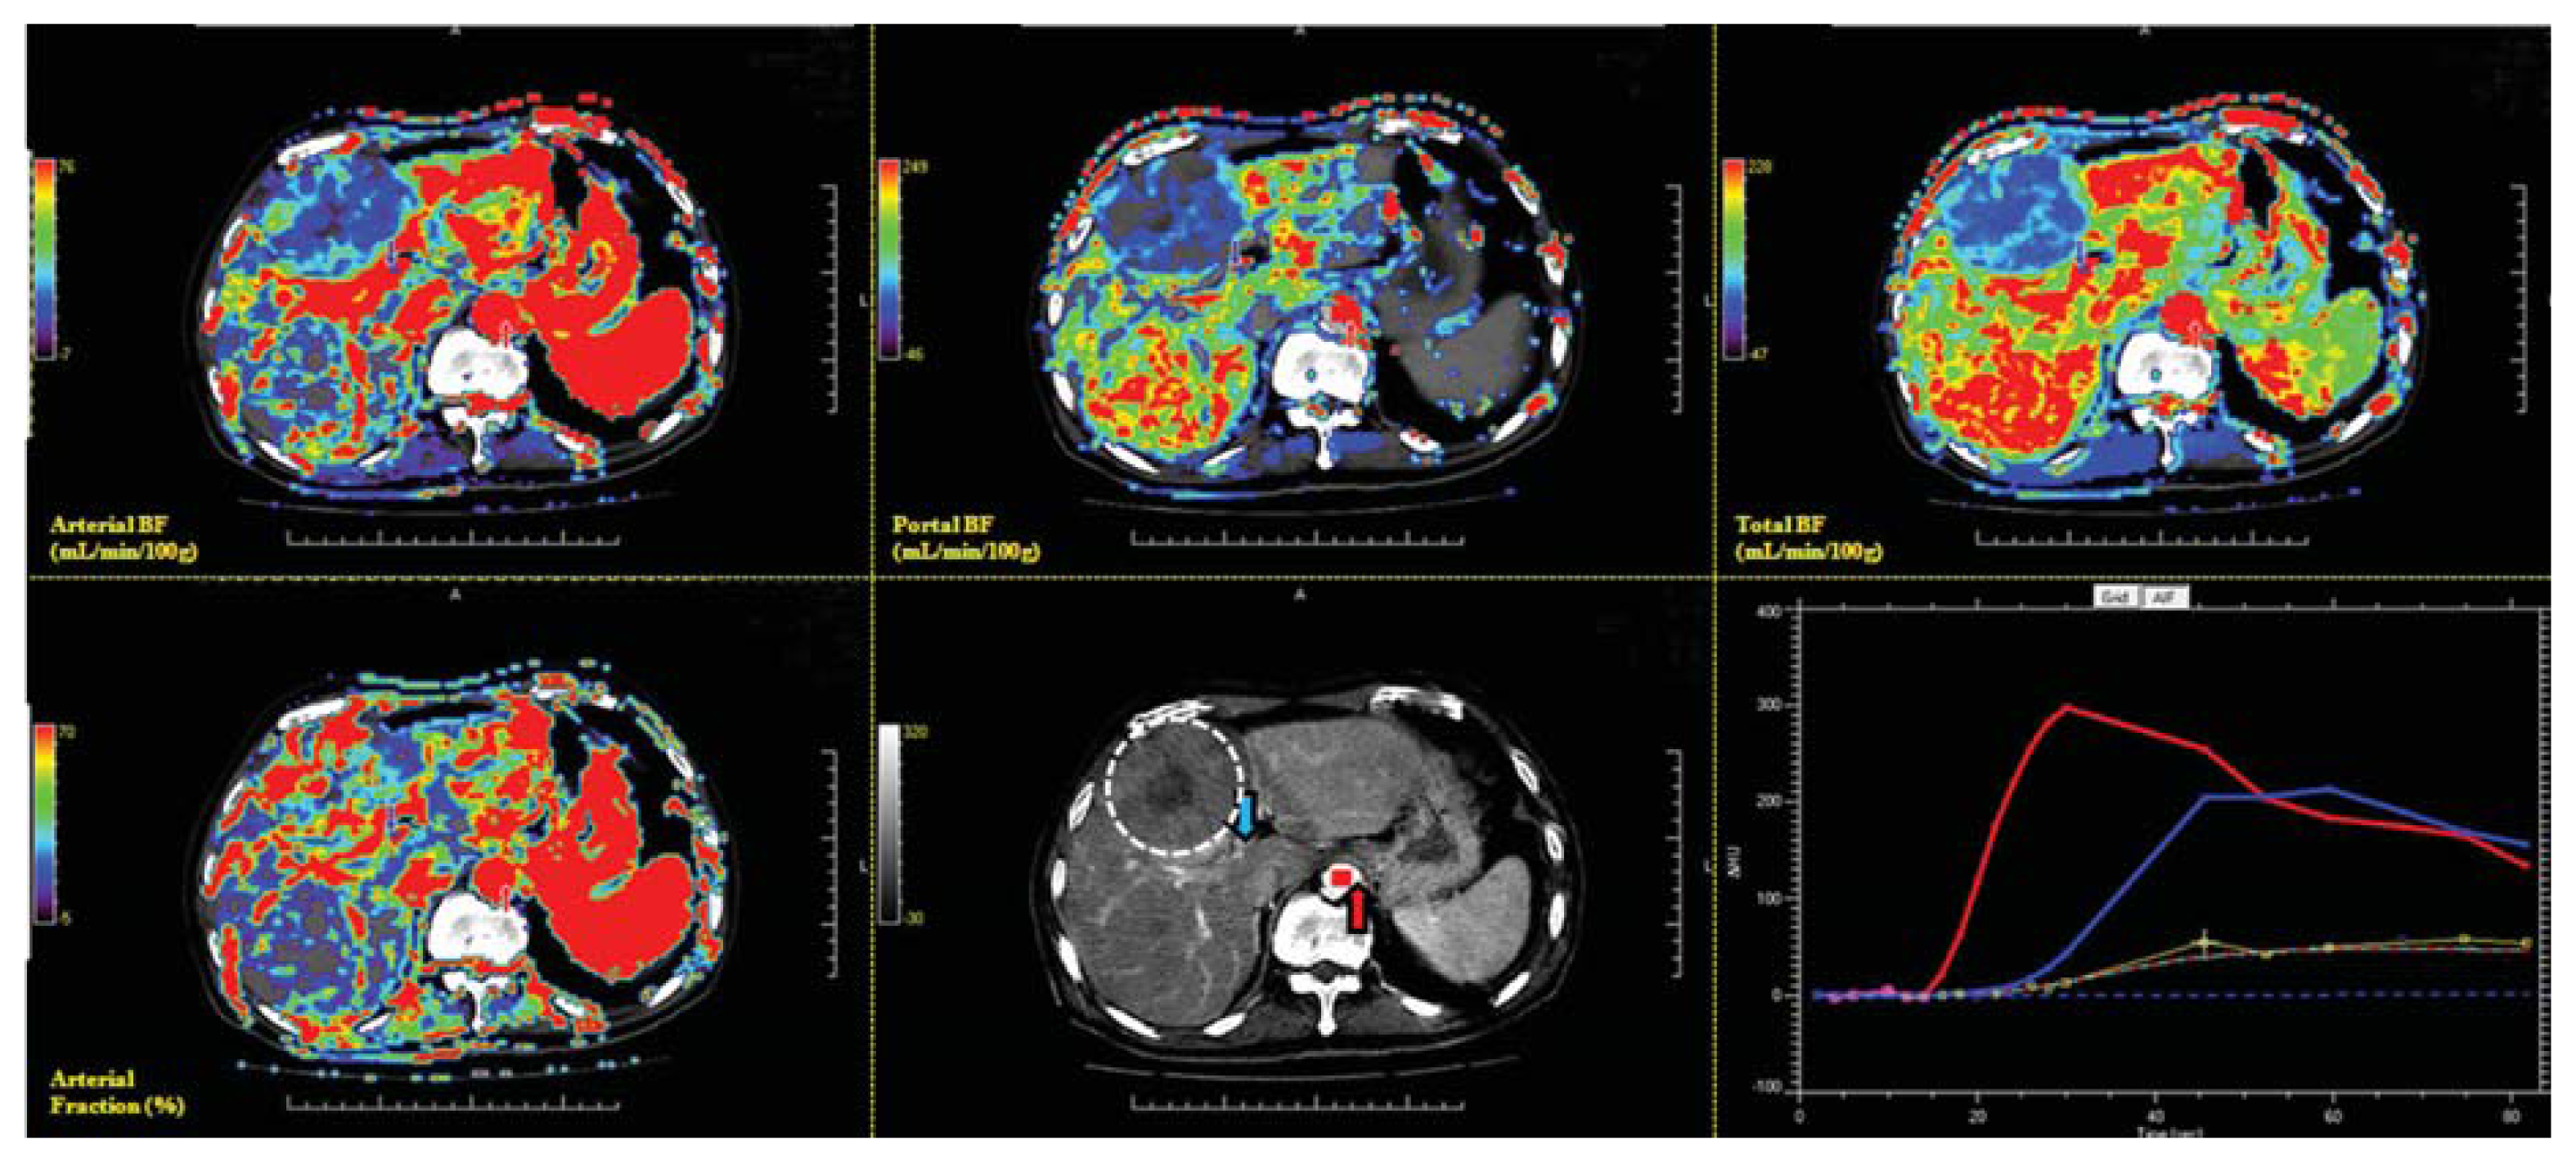

Data on the CT perfusion of the target HCC among 21 patients were analyzed at a commercially available workstation (MIStar, Apollo Medical Imaging, Melbourne, Australia) by two experienced radiologists (J.-S.H. and C.-P.C.), specializing in liver imaging for more than 14 years. Region of interest (ROI) placement was determined based on the consensus of the two radiologists. The definitions of the CT perfusion parameters and the models were used for generating functional CT perfusion maps. The commonly used two-compartment model regards the extracellular space and plasma as two compartments that are individually well mixed [53]. The Materne-van Beers Liver Model, including singular deconvolution analysis of the hepatic artery and portal flow, will be used in data analysis [53]. HCC vascular functional maps of total BF, arterial BF, portal BF, and arterial fraction were generated on a workstation (Figure 7). BF measured with CT perfusion imaging reflects the intratumoral BF supplied by the total dual BF (sum of arterial BF and portal BF), hepatic artery (arterial BF), portal vein (portal BF), and arterial fraction (arterial BF/total BF).

Figure 7.

Screen display of a target HCC on MIstar workstation with full functional images and enhancing curve of HCC and liver parenchyma. CT functional maps include arterial BF (upper left), portal BF (upper middle), total BF (upper right), and arterial fraction (lower left). Semi-automatic determination of the artery (red arrow) and portal venous input (blue arrow) are illustrated in the lower middle panel. In the lower right panel, the red curve represented the enhancing change of the target artery. The blue curve represents the target portal vein, and the yellow curve indicates the region of interest (ROI) of the HCC.